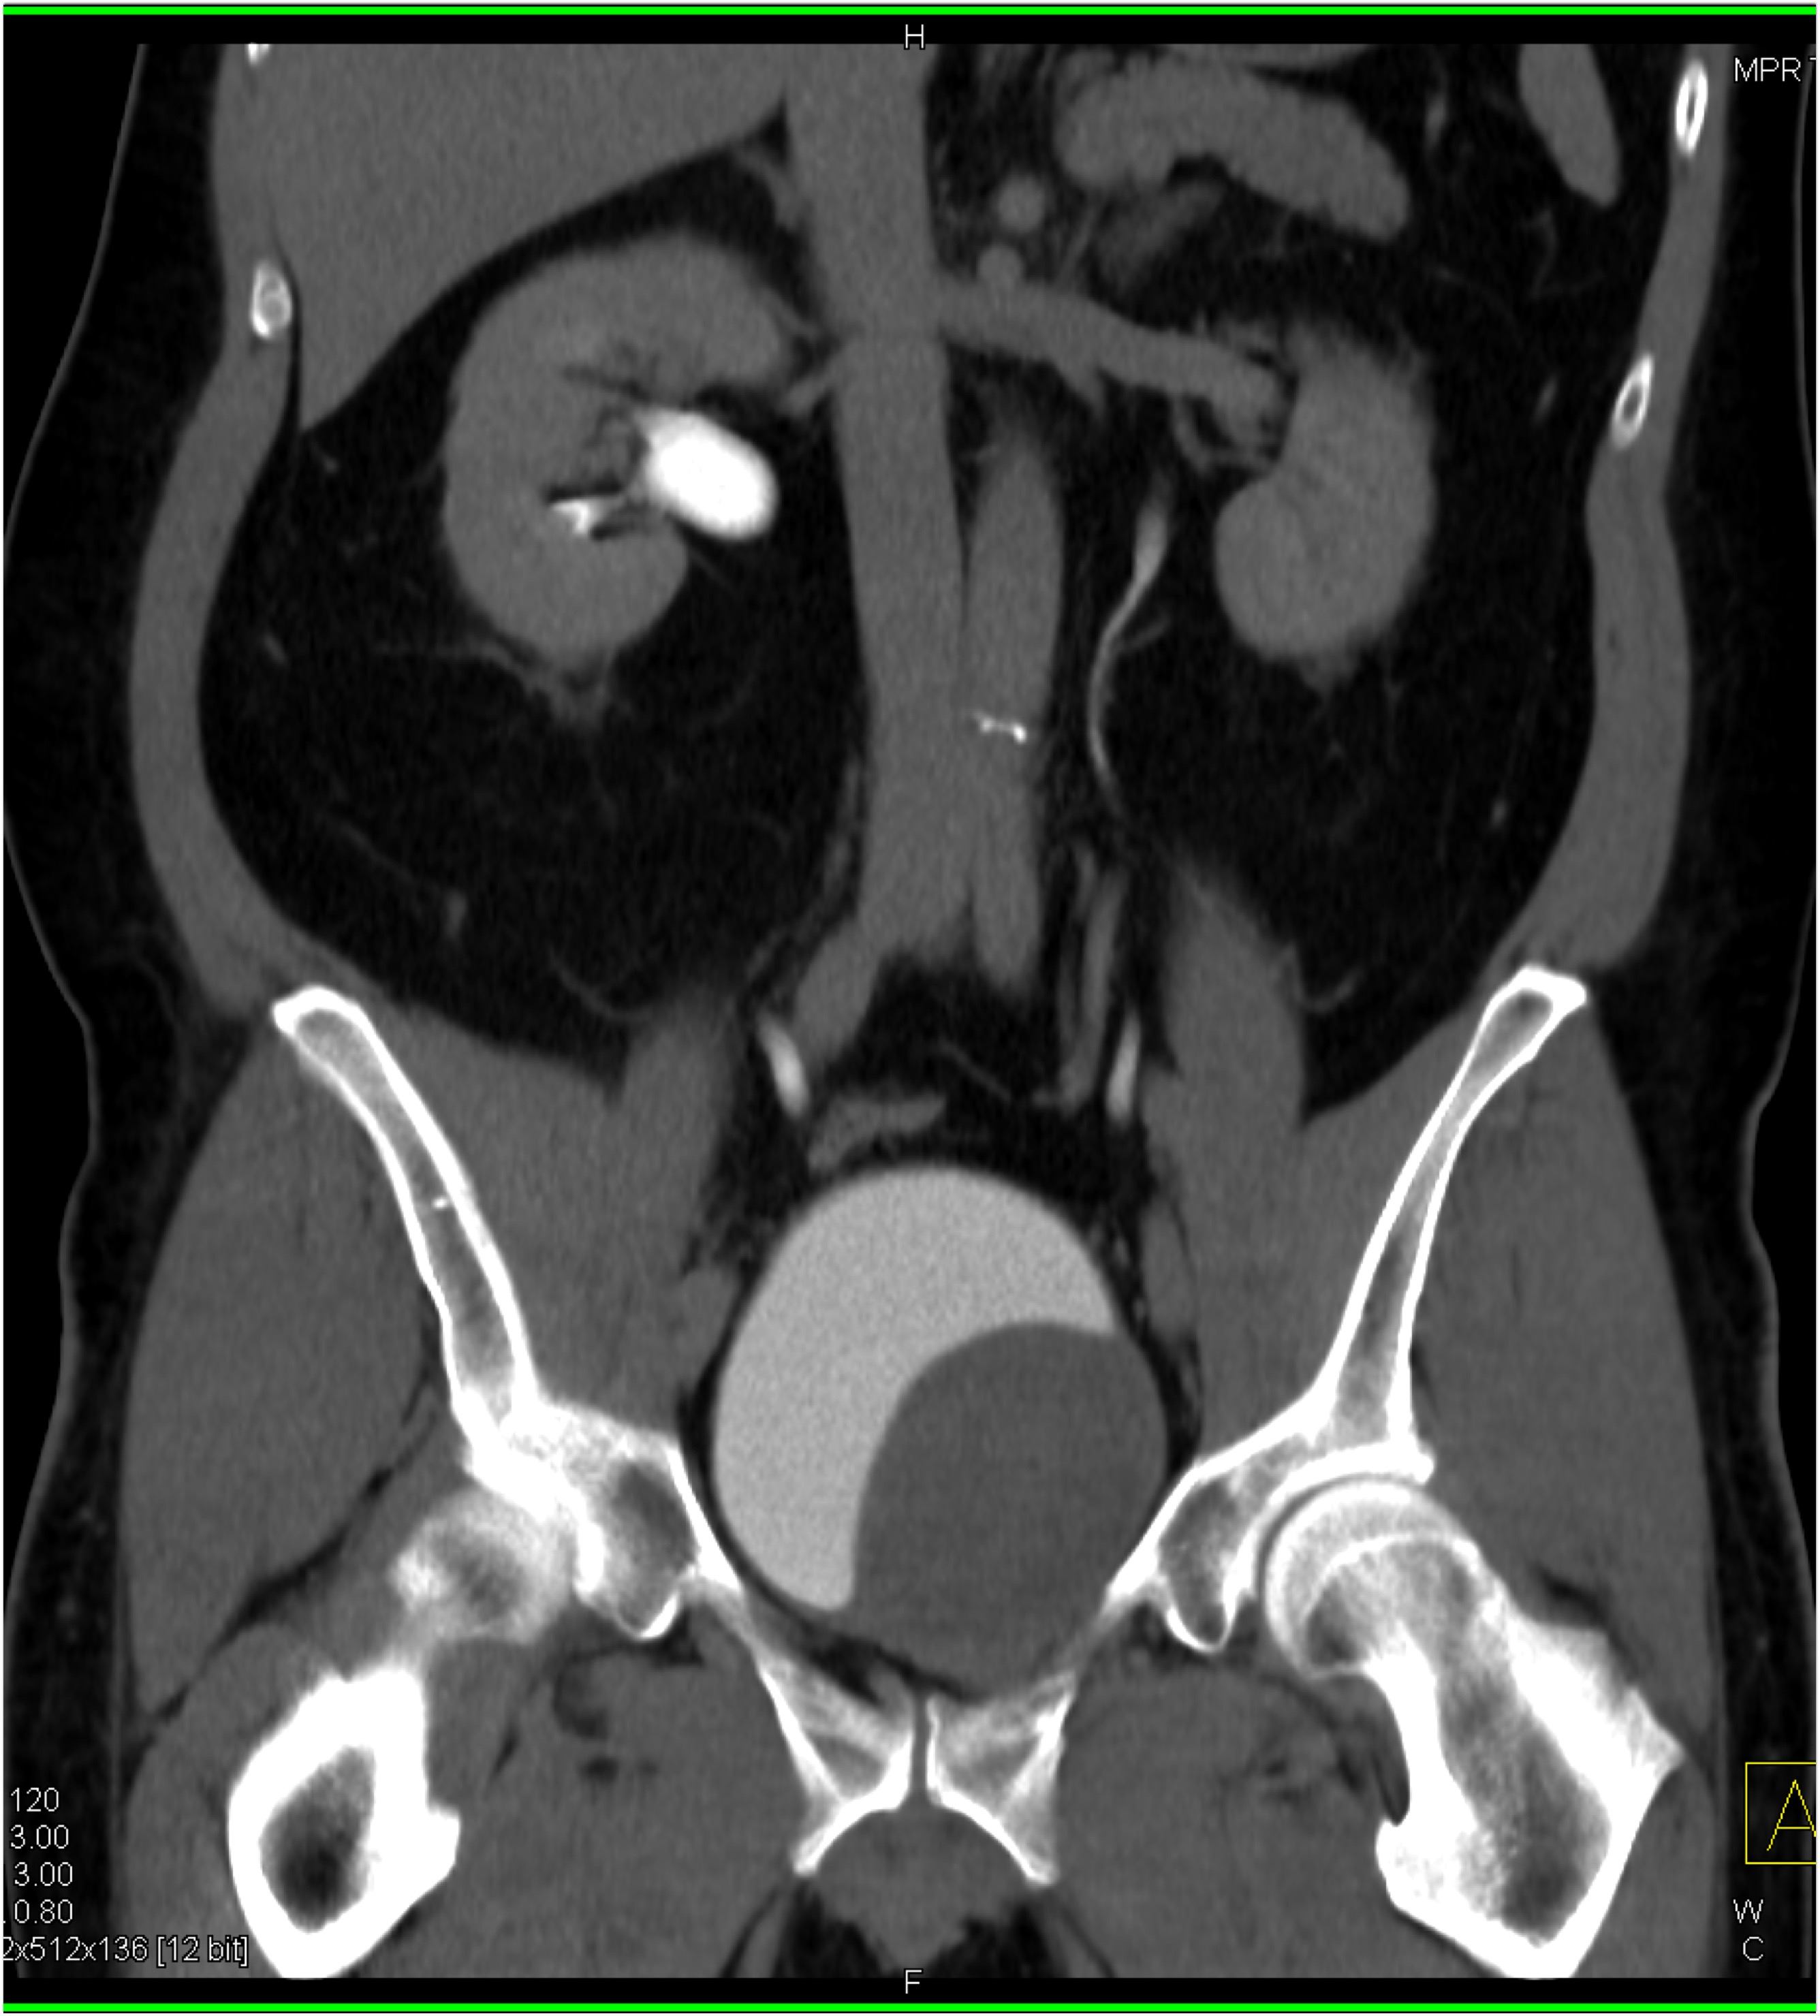

2) In this patient on dialysis for ESRD the best diagnosis is?

normal bypass graft

AV fistulae with aneurysms

vasculitis

infectious vascular disease